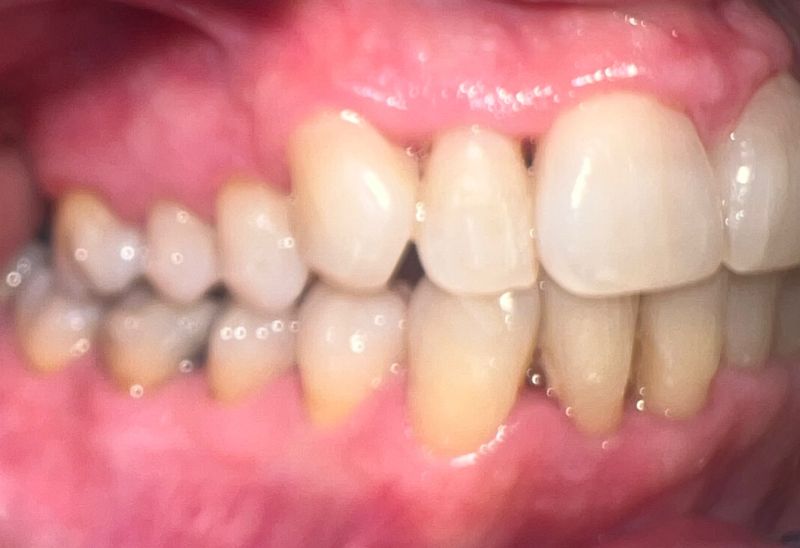

Prima e dopo l'apparecchio invisibile

In questa sezione mostreremo risultati reali ottenuti con l’ortodonzia invisibile a Roma. I cambiamenti riguardano non solo i denti, ma anche l’armonia del viso, la postura orale e l’autostima.